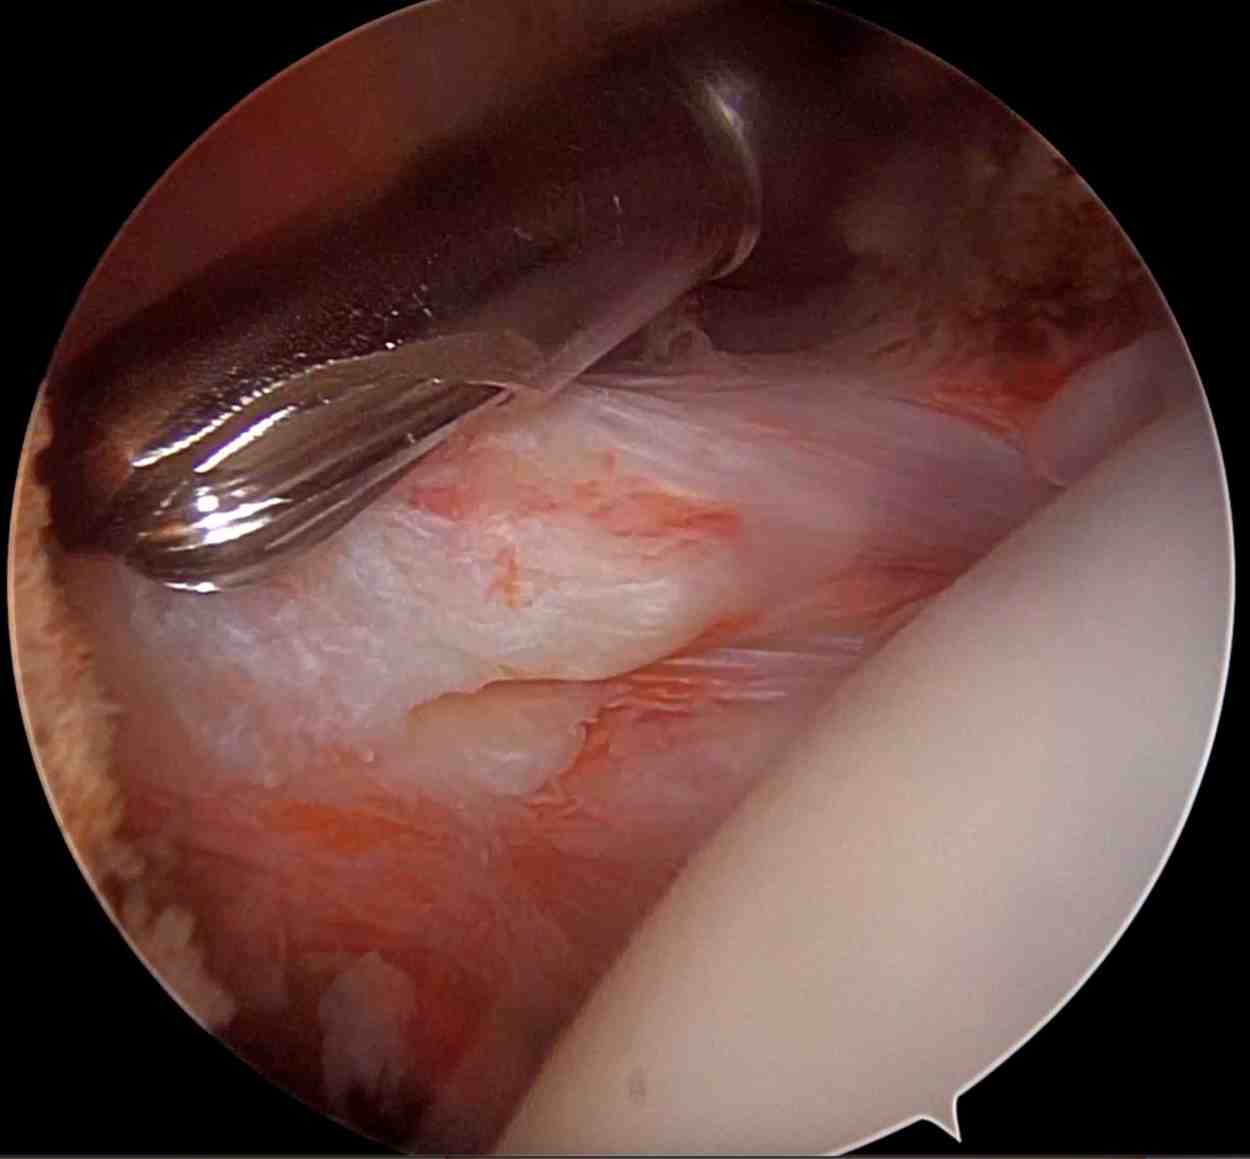

Shoulder Arthroscopy

Shoulder arthroscopy is a minimally invasive surgical procedure used to diagnose and treat problems within the shoulder joint. It involves the use of a small camera called an arthroscope, inserted through tiny incisions. This allows orthopaedic surgeons to visualize, diagnose, and repair a wide range of shoulder conditions with minimal trauma to surrounding tissues. It has got advantages over open surgery such as smaller incisions, less scarring, reduced post-op pain and swelling, shorter recovery time, lower risk of infection, better cosmetic result, earlier return to activities (depending on the procedure).

- Rotator Cuff Tears – Partial or complete tearing of the tendons.

- Labral Tears (e.g., SLAP or Bankart lesions) – Often related to shoulder dislocations or overhead sports.

- Loose Bodies or Cartilage Damage – Clean-up or debridement of the joint.

- Biceps Tendon Disorders – Such as biceps tenotomy or tenodesis.